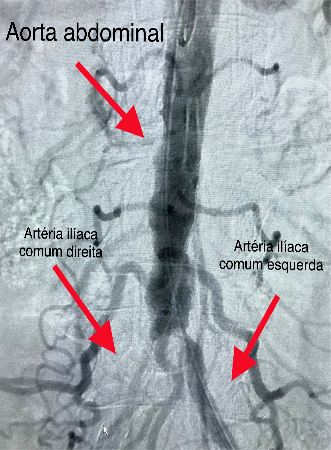

Tratamento de Aneurismas de Aorta, Periféricos ou Vicerais

É o tratamento de artérias dilatadas por métodos endovasculares pouco invasivos. O procedimento pode alterar de acordo com a região localizada, do tamanho e da condição do aneurisma. Atualmente a cirurgia vascular dispõe em seu arsenal para o tratamento de aneurismas, um método seguro e menos invasivo que a cirurgia convencional. O tratamento endovascular para aneurismas de aorta, viscerais e periféricos possibilita uma melhora na qualidade de vida dos pacientes de uma forma menos agressiva, objetivando evitar as principais complicações dessas doenças. São utilizados dispositivos de implante totalmente percutâneo e o procedimento é realizado em local específico para estes casos. Após detalhada análise de exames complementares: ultrassom, angiotomografia, angiorressonância, o cirurgião vascular opta pela melhor alternativa de tratamento baseado na anatomia da doença e no perfil de cada paciente.